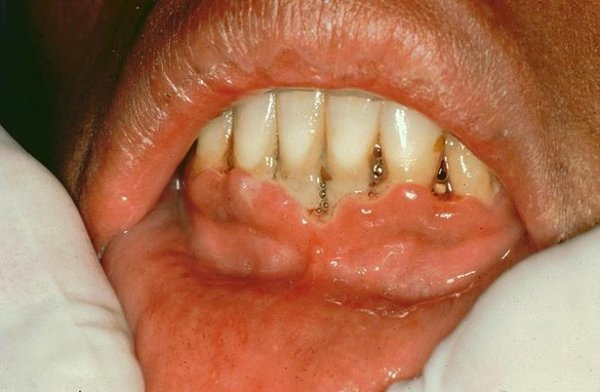

Фиброзный тип

Во время такого вида заболевания происходит поражение всего нескольких зубов. Сильного отёка не наблюдается, припухлость может быть только незначительной, у основания десны.

Фото 4. При поражении полости рта фиброзным гингивитом изменение тканей может происходить как с внешней, так и с внутренней стороны.

Цвет десны остаётся неизменным, в редких случаях меняется на серый. Отсутствуют болезненные ощущения, кровоточивость, но происходит увеличение объёма десны.